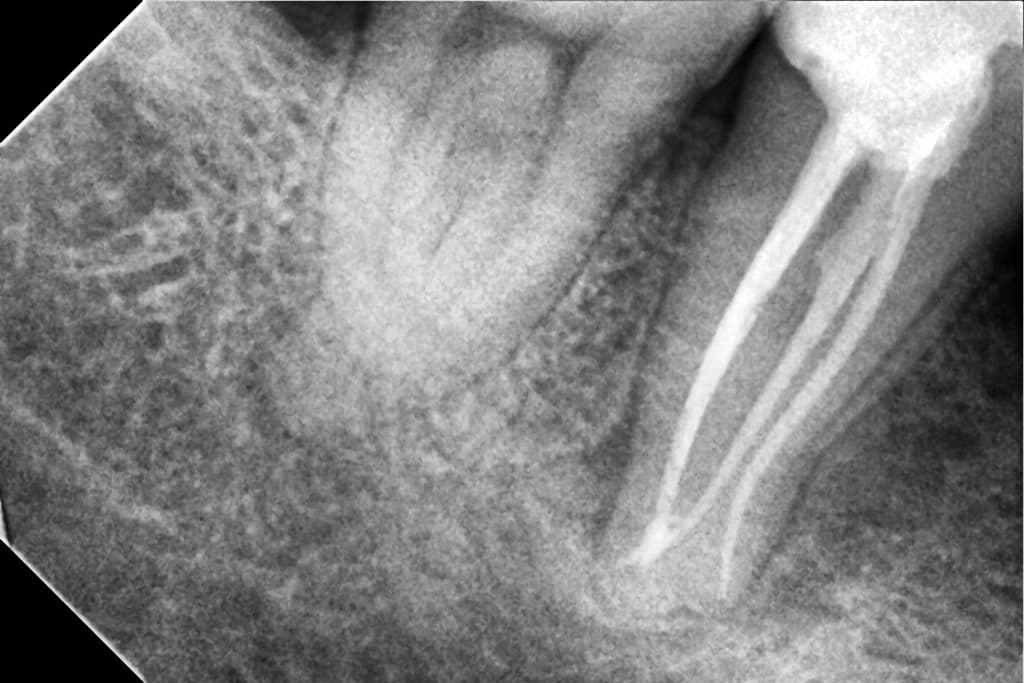

RCT for tooth no.47 with J shape lesion!

The canals was C shape in configuration

Diagnostic x-ray